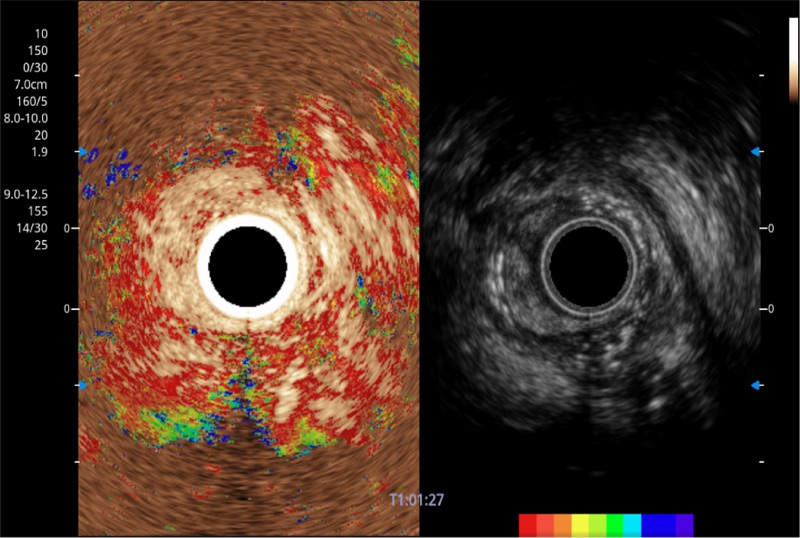

可人為將灰階圖像轉(zhuǎn)變成彩色的顯示方式,增強(qiáng)人眼對(duì)于不同回聲強(qiáng)度的敏感度,主觀上增加了圖像分辨率

微米成像技術(shù)提升了對(duì)組織斑點(diǎn)噪聲信號(hào)的抑制能力,并進(jìn)一步強(qiáng)化邊界信息,從而獲得信噪比更優(yōu)、邊界更清楚銳利的圖像

隨著組織深度的變化,超聲接收頻率進(jìn)行智能匹配跟蹤,確保圖像中、遠(yuǎn)場(chǎng)良好的穿透力以及整場(chǎng)一致的分辨力,從而得到均一的畫(huà)質(zhì)